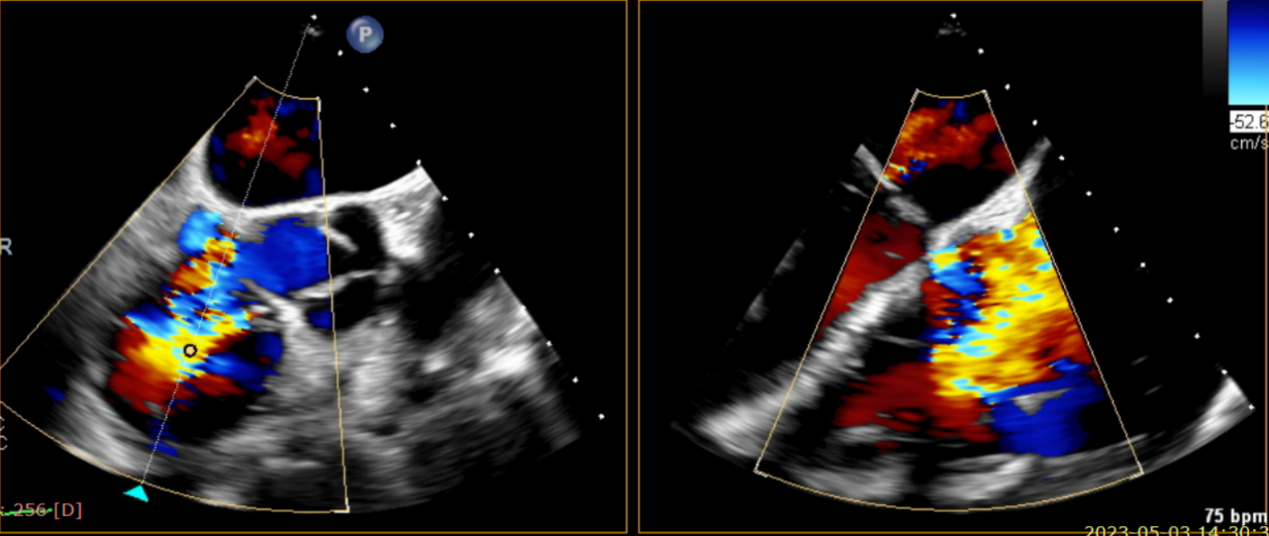

術前超聲提示大量三尖瓣反流

術中輸送器在超聲引導下調整位置

術后超聲提示無瓣周漏